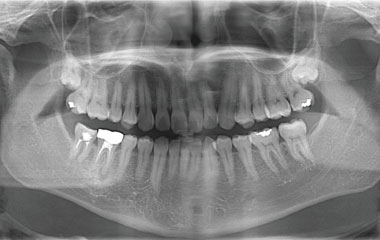

阿倍野区昭和町の歯医者 ひだまり歯科では、専用機器と技術を駆使した「世界基準の根管治療」を行い、感染源を徹底的に取り除きながら健康な神経をできるだけ残し、歯を長く維持できるよう努めています。

根管は歯の中を通る非常に細い管で、肉眼では確認できません。そのため、治療時には拡大鏡を使用し、細部までしっかり確認しながら治療を進めています。さらに、死んでしまった神経や血管を除去するために、柔軟性が高く複雑な根管にもフィットするNiTi(ニッケルチタン)ファイルを使用し、感染部位の取り残しを防ぎ、徹底的に清掃・消毒を行います。さらに、ラバーダムで治療中の感染を防ぎ、再発リスクを最小限に抑えています。

拡大鏡による拡大視野で、肉眼では見えない感染部位を確認